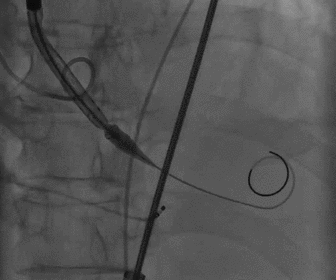

根部造影

球囊预扩

胶囊腔定位

瓣膜释放

造影观察瓣膜形态